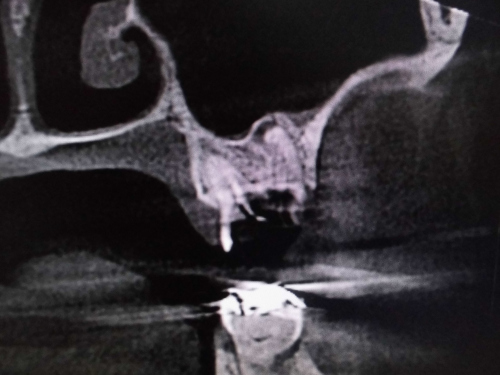

上顎洞との位置関係が確認できます。

CTでは近心の第二根管も確認できます。

原因が頬側近心根とわかりました。上顎洞粘膜が肥厚しているのもわかります。